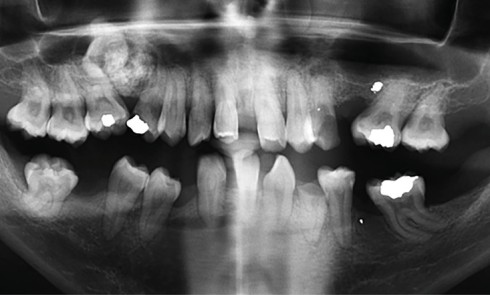

Article réservé à nos abonnés L’extraction implantation immédiate en secteur postérieur associée à la mise en œuvre du pilier SSA

Depuis plusieurs années, l’extraction implantation immédiate apparaît comme une stratégie de traitement arborant un nombre fleurissant de publications scientifiques [1,...